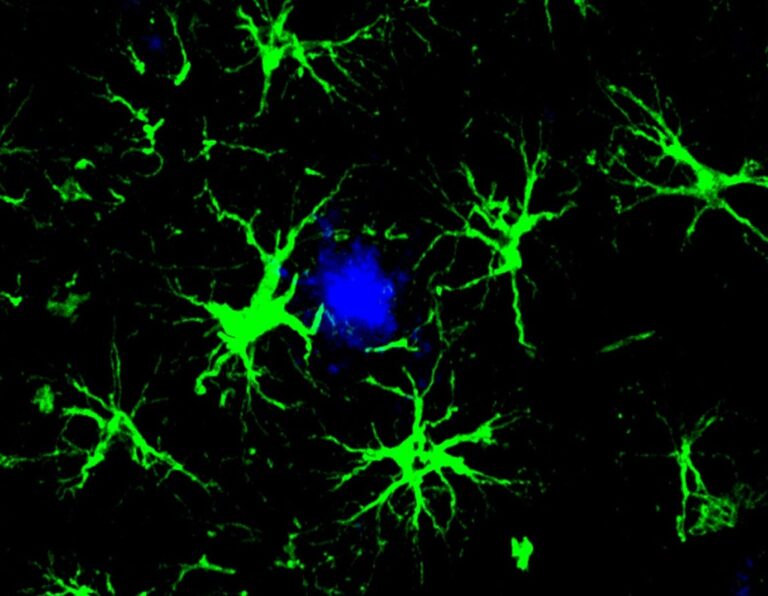

Γενετικά τροποποιημένα εγκεφαλικά κύτταρα «τρώνε» τις πλάκες του Αλτσχάιμερ

Ερευνητές στο Washington University μετέτρεψαν αστροκύτταρα — κύτταρα-υποστήριξης του εγκεφάλου — σε μηχανές καταστροφής της…